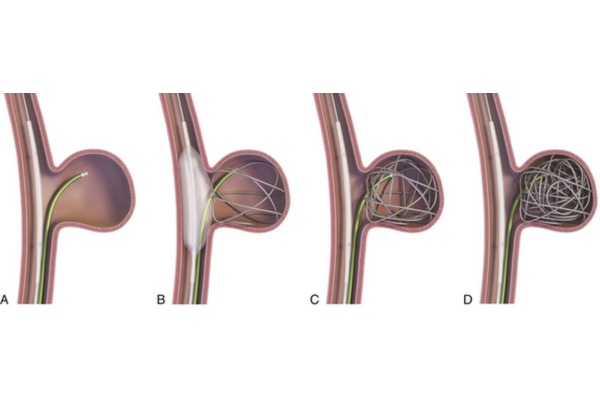

Minimally invasive technique using soft coils to block aneurysm flow, preventing rupture and ensuring long-term vascular stability.

Aneurysm coiling is a minimally invasive procedure used to treat brain aneurysms by preventing rupture. It is performed when weakened blood vessels balloon and pose a serious risk of bleeding.

Using thin catheters, soft coils are placed inside the aneurysm to block blood flow, reduce pressure, and safely prevent future bleeding.